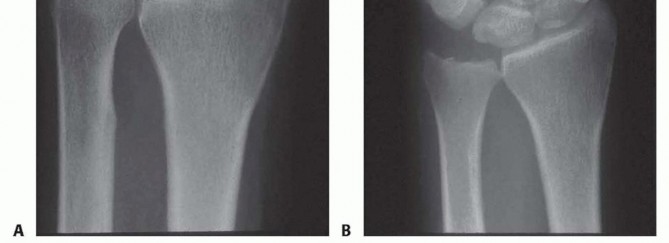

FIG 3 • B,C. T1 and T2-weighted MRIs of a wrist with ulnar abutment. Note the hyperintense signal on the T2 sequence at the ulnar proximal lunate, indicative of intraosseous edema and microtrabecular trauma secondary to chronic impaction.

The MRI allows us to map the extent of the central perforation. If the tear is small, we know we will need to enlarge it during the débridement phase to gain adequate access to the ulnar dome for the subsequent wafer resection. Furthermore, the MRI helps rule out concomitant pathologies, such as Kienböck's disease or occult carpal fractures, which would drastically alter our surgical algorithm.